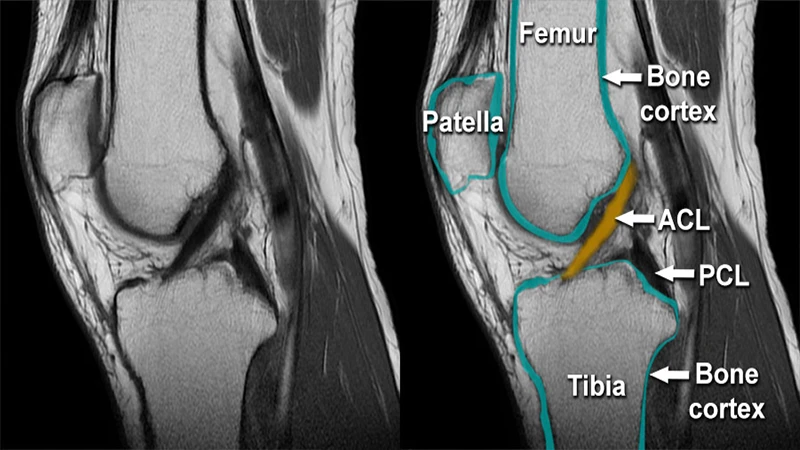

• Musculoskeletal (MSK): MRI is used to diagnose injuries to ligaments, tendons, cartilage, and muscles, such as a torn ACL in the knee or a rotator cuff tear in the shoulder.

An MRI image of a human knee showing the intricate detail of the ligaments and soft tissues, possibly with a tear indicated